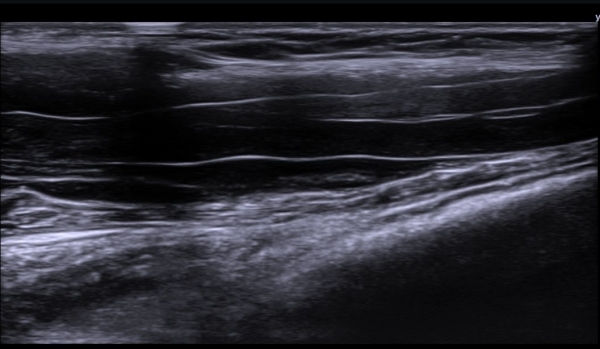

¼â°ñ¾Æ·¡¿¡¼­ »ó¿Ï½Å°æÃÑ Á¾´Ü¸é°Ë»ç¿¡¼­ »ó¿Ï½Å°æÃÑ ¿ÜÃø ²ö(lateral cord)ÀÇ Àú¿¡ÄÚ ºÎÁ¾ÀÌ

°üÂûµÈ´Ù(»çÁø 7).